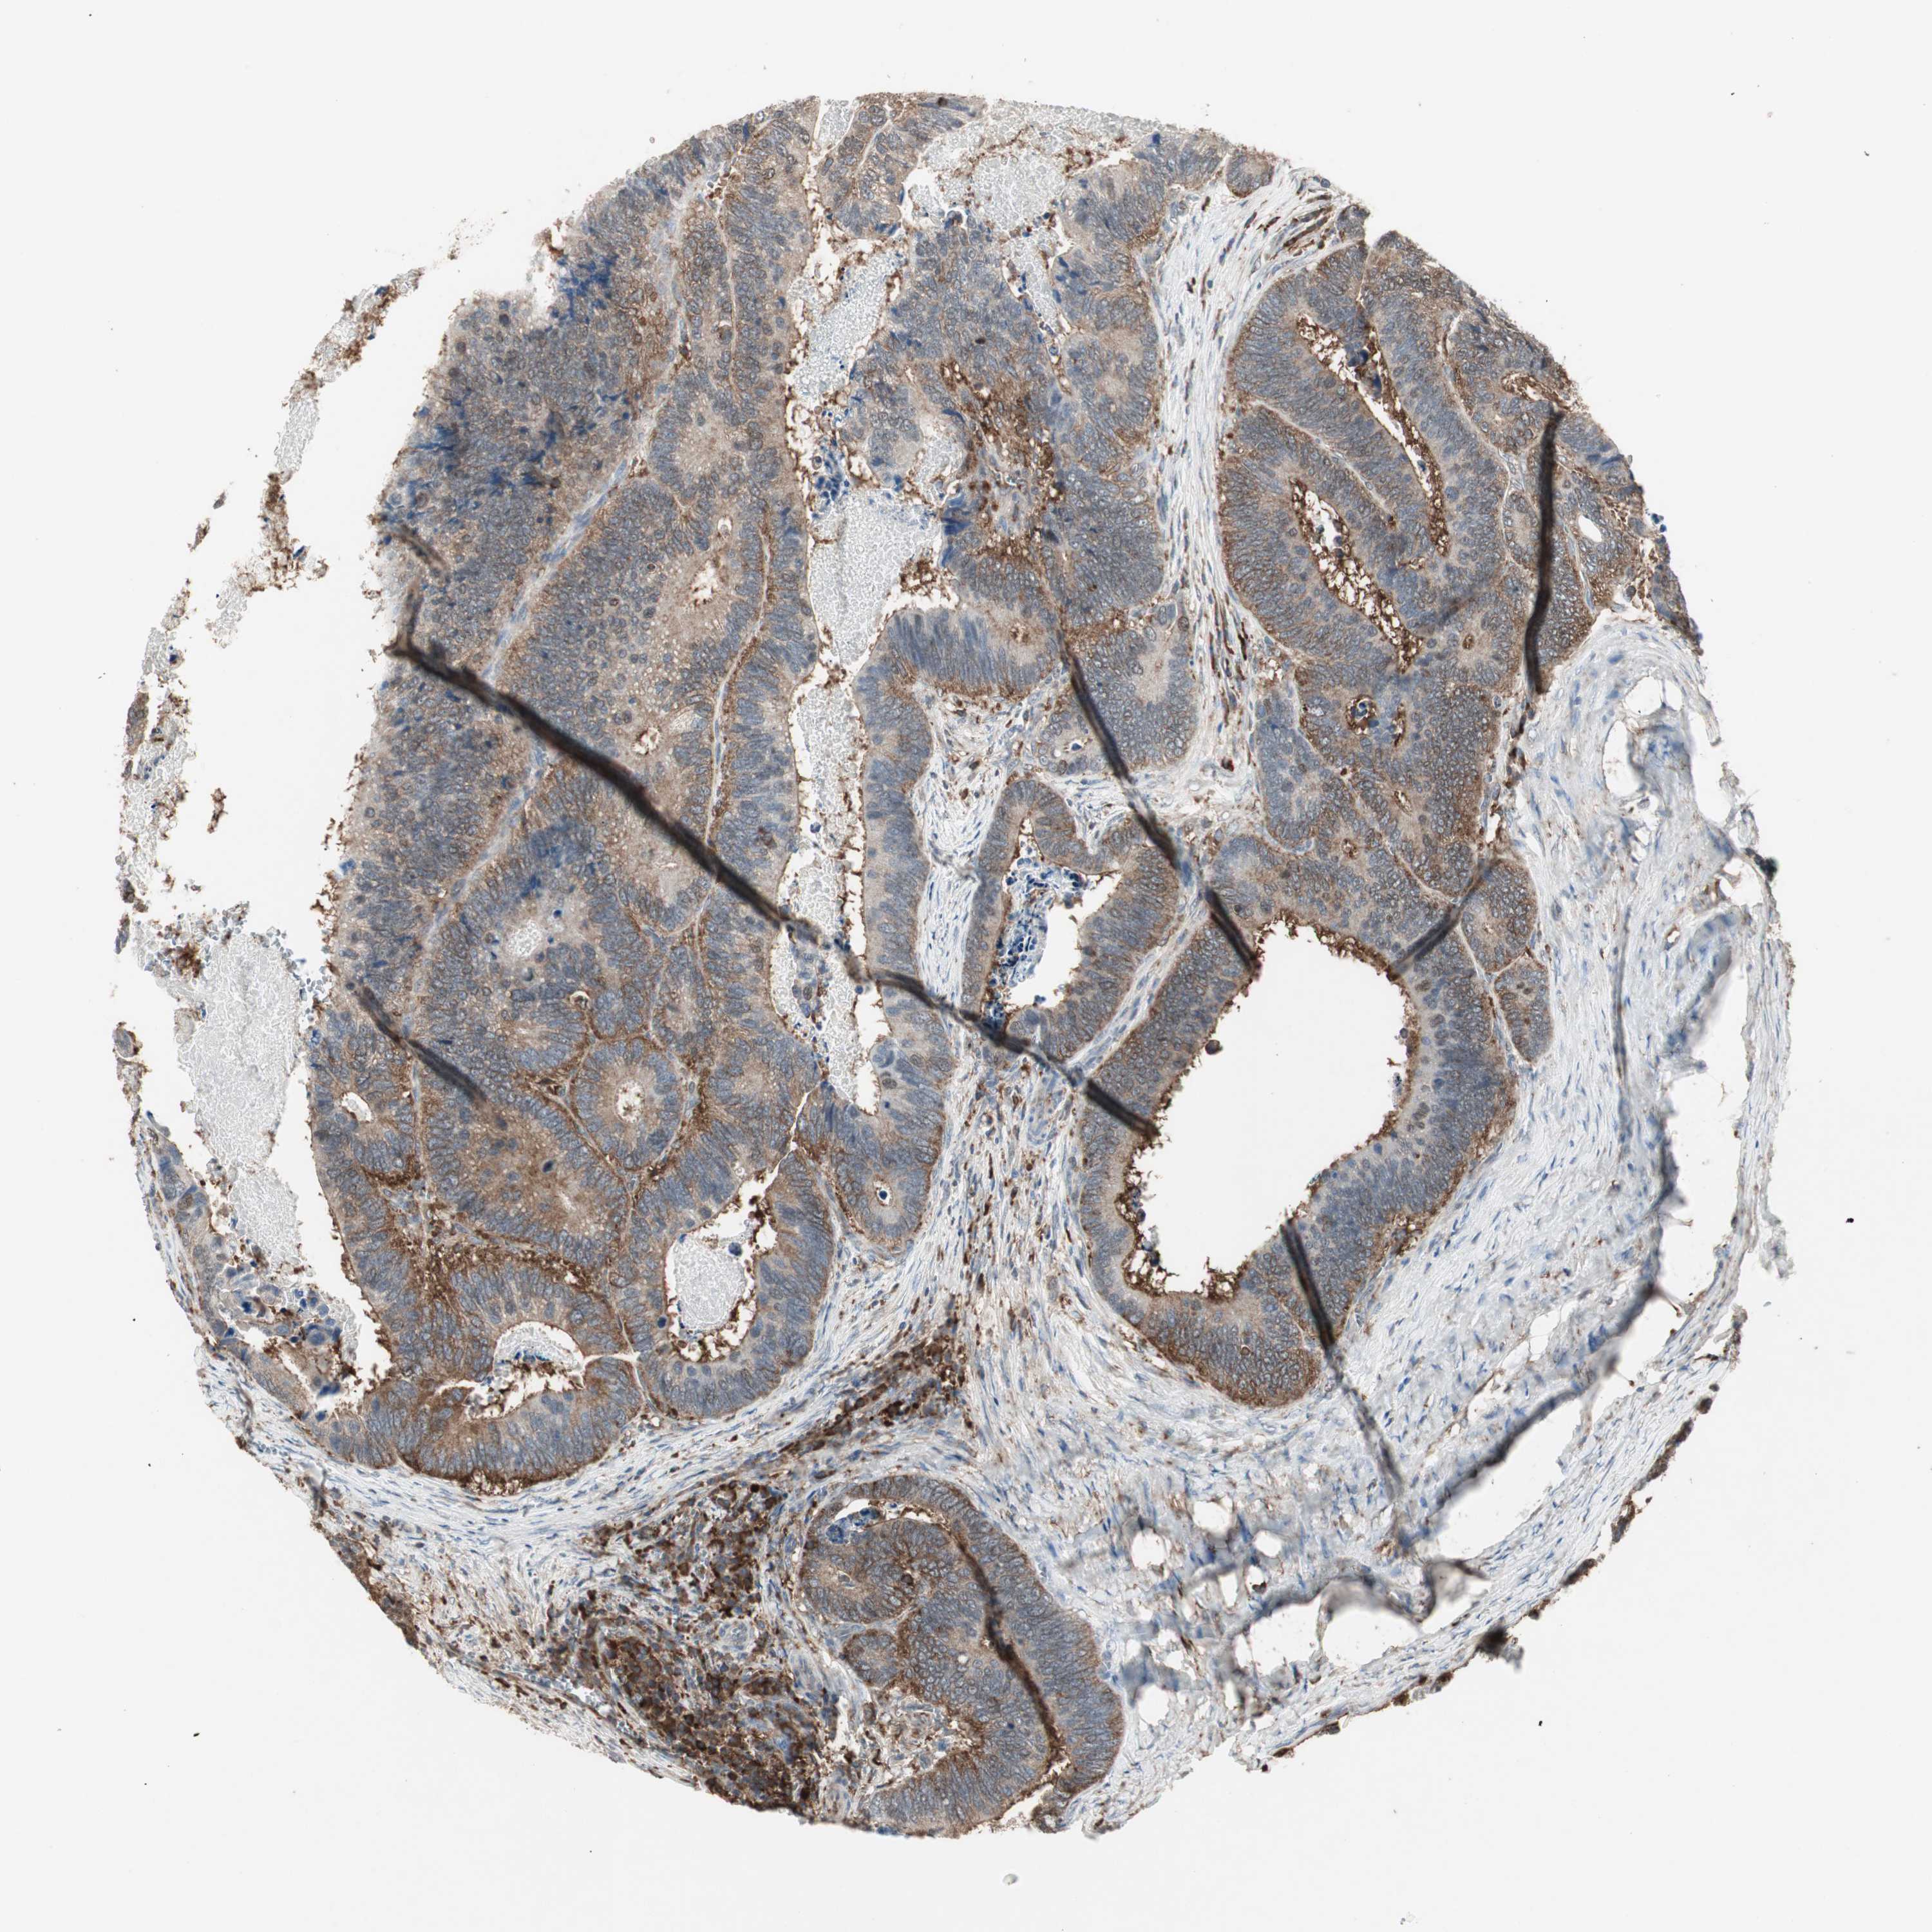

CANCER COLORECTAL CANCER Show tissue menu

Colorectal cancer

Human cancer

Colon adenocarcinoma